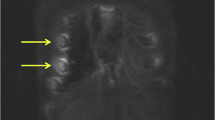

ALTHOUGH scurvy was probably the first clearly defined nutritional disease and active antiscorbutic material was the first of all the vitamins to be crystallized and synthesized, the biochemical function of ascorbic acid in synthesis of collagen has only recently been identified. Some of the proline residues of the collagenous poly-peptide are hydroxylated to form hydroxyproline, and ascorbic acid is a co-factor for the hydroxylating enzyme1. Most pathological findings in scurvy can be attributed to a restriction in ability to synthesize collagen of bone, teeth and other connective tissues. Some manifestations occasionally found in infantile scurvy are more prominent in adult scurvy and are difficult to explain by a restriction in ability to synthesize collagen of connective tissues. For example, the cutaneous haemorrhages or “scorbutic spots” appearing spontaneously about hair follicles are one of the cardinal signs of adult scurvy2.